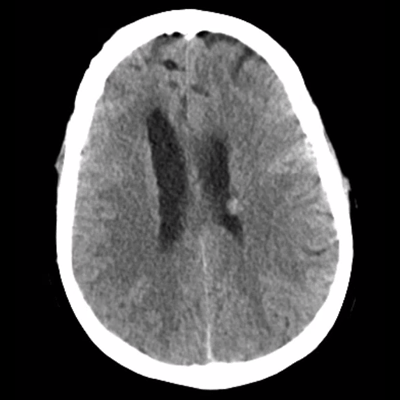

She woke up this morning and her legs "gave out" when she walked to the bathroom. Her hands shook bilaterally. She tried to speak, but her husband said she was "garbled" and nonsensical. Symptoms stopped once she got back in bed. She was able to speak short sentences. This episode lasted about two minutes in total. Her husband drove her to the ED. There, initial vitals are notable for BP 179/73, HR 63, SpO2 99% on room air, T 36.4C. Initial labs are notable for WBC 13, Hb 12, Plt 250, Na 133, Cr 0.7, uNa 179, uOsm 941, sOsm 274. A non-contrast HCT was obtained and is shown below. Her neurologic exam remains slightly abnormal: she is somnolent but does briskly awaken to verbal stimuli. She has no clear focal weakness or hypoesthesia. You were then consulted.

HCT part 1 HCT part 2 HCT part 3

Looking at her non-contrast HCT now, there's nothing new in terms of acute hemorrhage or large-territory infarction, nor overt vasogenic edema. Now we should compare this to the prior scan. It's not shown well in these example slices shown here, but her ventricular caliber was very subtly larger as compared to the MRI, most noticeable with the slightly larger temporal horns and third ventricle.

Our leading diagnosis at this point is epileptic seizure. You hear that our neurology colleagues are already recommending repeat imaging and EEG, and they'll also start levetiracetam. Repeating an MRI is reasonable because she's already demonstrated cancer progression in spite of her therapy, and she's now having new symptoms. Her HCT doesn't clearly reveal anything that requires acute neurosurgical intervention. She has expected post-operative changes related to her frontal lobe metastasis resection. Her ventricles are questionably larger, but because of the temporal relationship with the steroid taper, you don't think this is responsible for her presenting symptoms. Her ependymal nodule certainly isn't the major contributor of her problems.